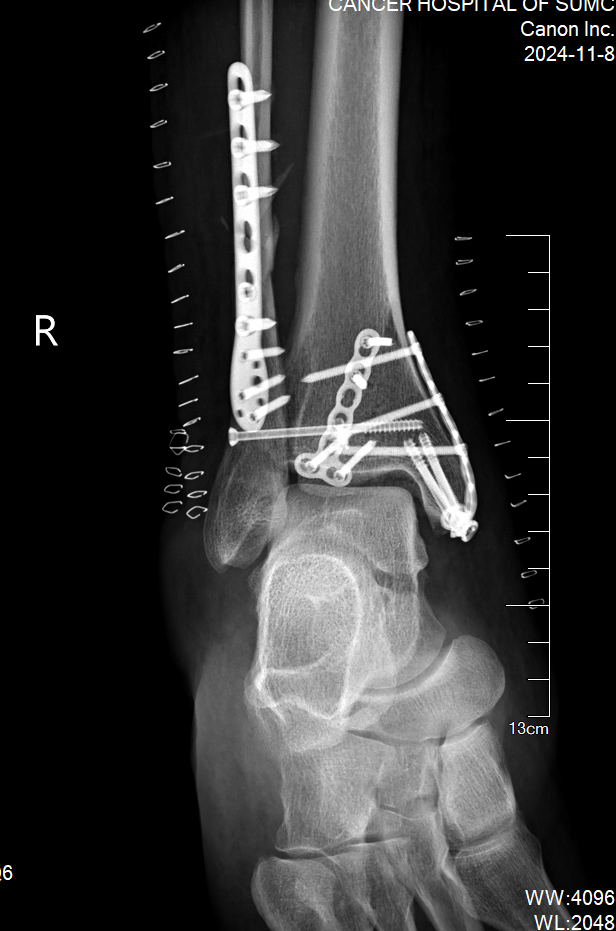

在这10天里,医院骨科医护团队对患者进行了精心的照料,并时刻同患者保持积极的沟通。随着右踝关节肿胀的逐渐消退,手术的时机也日益成熟。最终,凭借精湛的技术,患者右胫腓骨远端骨折达到了解剖复位。

图片 4.png

患者术后复查骨折端解剖复位